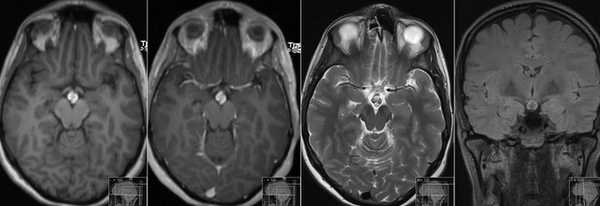

Фото томографии аденомы гипофиза

Опухоль гипофиза на МРТ выглядит как участок округлой формы с четкими границами

Макроаденома гипофиза на снимке МРТ

Выявление микроаденомы гипофиза с помощью МРТ: изображения в разных проекциях

Гигантская аденома гипофиза на МРТ